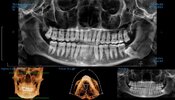

You don’t look like you have an overbite to my in these scansThis is from a CBCT scan

FYI your name is in the top left corner may want to redact thatThis is from a CBCT scan

i agree, or it's at most a very slight overbiteYou don’t look like you have an overbite to my in these scans

It is… humans are supposed to have slight overbite, like 3-4mm of overlap with front incisors over bottom incisors. His teeth look decent too… I can’t tell if the photo of his skull was not oriented properly or if he has a cant?i agree, or it's at most a very slight overbite

The one thing is looking at the frontal view of his x-ray, it appears his facial midline may be off, but I can’t say for surerealistically speaking, your bite is pretty good so getting such heavy treatment could easily make your skeletal imbalance look worse + the reason why your midface appears "sunken" is because your infras are recessed, your zygo projection is good tho